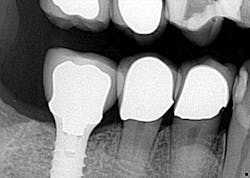

Hygiene. It can be agreed upon that if an implant can’t be kept clean, then the potential for failure and difficulties rise exponentially. A 90-degree angle between the implant and crown is virtually impossible to keep clean and maintain. As amazing as some hygienists are, it is impractical to expect that a curette can get into that space to clean it without making hamburger of the tissue. The implants were cemented on, so they are not easily retrievable. The emergence profile is nonexistent. Do natural teeth look like this? I would submit that when restoring implants, it is our job to mimic the shape and emergence profile of natural teeth as closely as possible. When we don’t, then we lose the inherent cooperation and benefits that the tissue can provide. To help the parents understand this concern, I showed them an example of a traditional implant vs. the “pumpkin on a toothpick” implant. The side-by-side comparison spoke for itself.

vs.